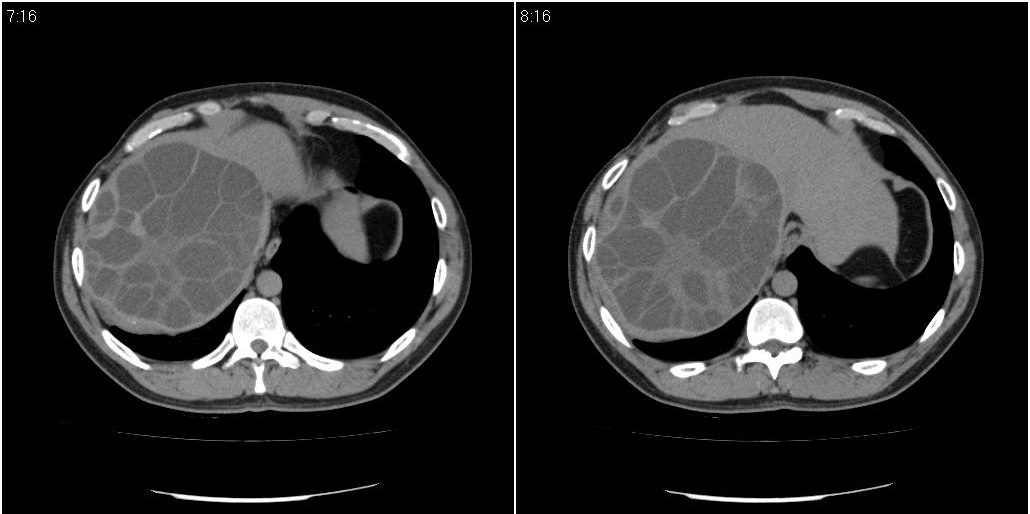

该患者70岁男性,手术后10年,现复查。2008年6月份本人曾经发过一极其类似的病例,只是部位略有差异。

多囊肝

肝脏多房性包虫囊肿

水上浮莲征,肝包虫囊肿。

大囊套小囊!肝脏多房性包虫囊肿

谢楼主提供这么典型病例。